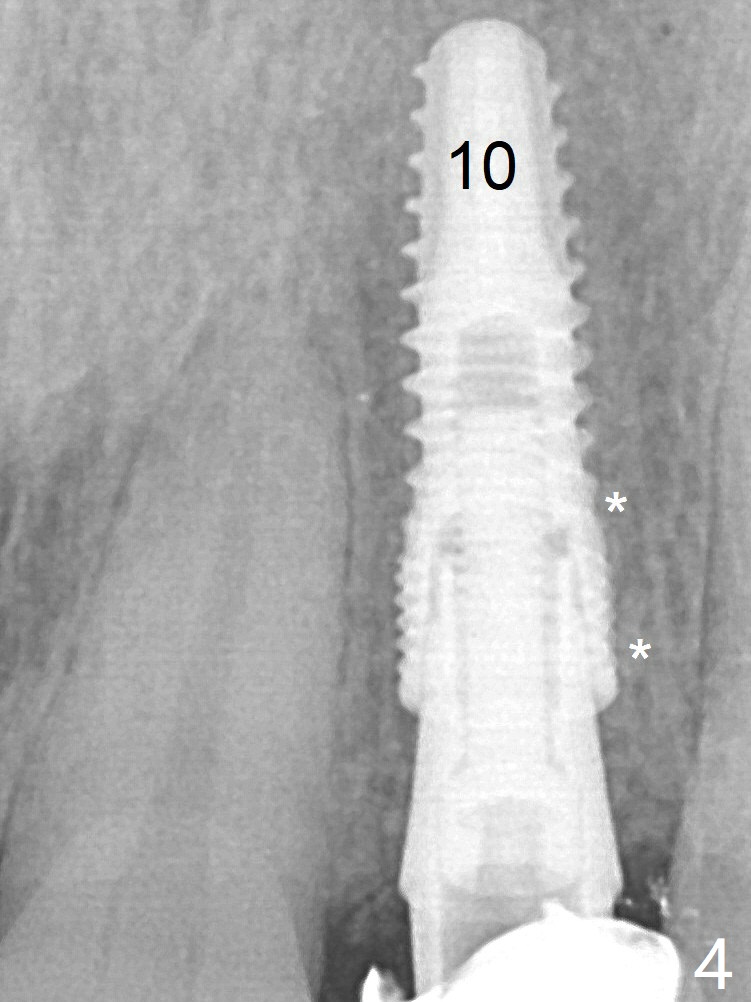

After a 3.8x12 mm SM implant is placed (Fig.4), allograft is packed in the periimplant space (*). The patient returns for impression 3.5 months postop (Fig.10).